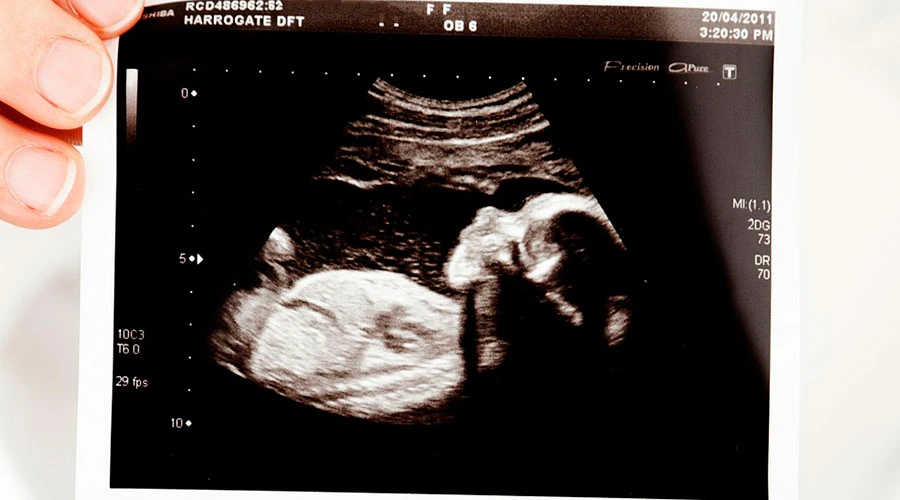

Entre los problemas que preocupan a la hermana Mercy están las presiones que empujan a las mujeres hacia el aborto, que incluye el diagnóstico mediante pruebas prenatales.

La religiosa indicó que si bien las pruebas prenatales son cada vez más precisas, "a veces Dios hace milagros en el vientre de la madre que son increíbles".

La hermana Mercy señaló que ha "tenido muchas ocasiones en las que hay pruebas irrefutables que muestran que el bebé va a tener una anomalía realmente difícil", y recordó el caso de un bebé con un diagnóstico prenatal preocupante por el que "todo el mundo rezaba", y que nació totalmente sano.